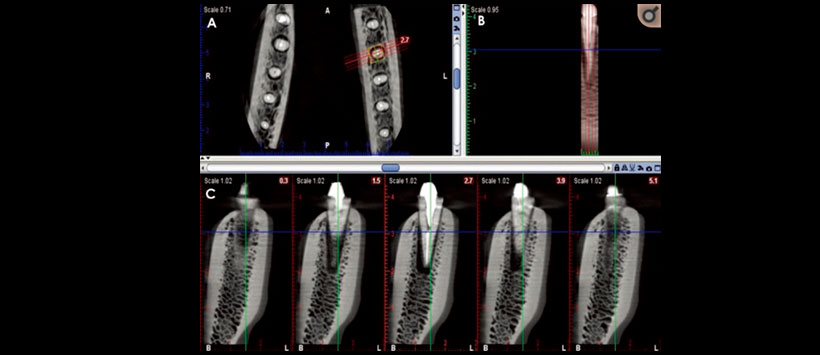

El posicionamiento periférico del objeto sin el algoritmo MAR produjo la sensibilidad más alta para el primer observador (66.7%). Para el segundo y tercer observador, una posición central mejoró la sensibilidad, con o sin el algoritmo MAR. En presencia de postes metálicos, la posición central del objeto en el FOV aumentó significativamente la sensibilidad y la precisión del diagnóstico en comparación con la posición periférica. (Figura 1)

Siendo la precisión diagnóstica fue mayor con el posicionamiento central (Figura 2) que con el posicionamiento periférico, independientemente de si se aplicó el algoritmo MAR (Figura 3). Sin embargo, el efecto del algoritmo MAR fue más significativo con el posicionamiento central que con el posicionamiento periférico del objeto en el FOV. La experiencia clínica y la experiencia de los observadores pueden servir como un factor de confusión a este respecto.